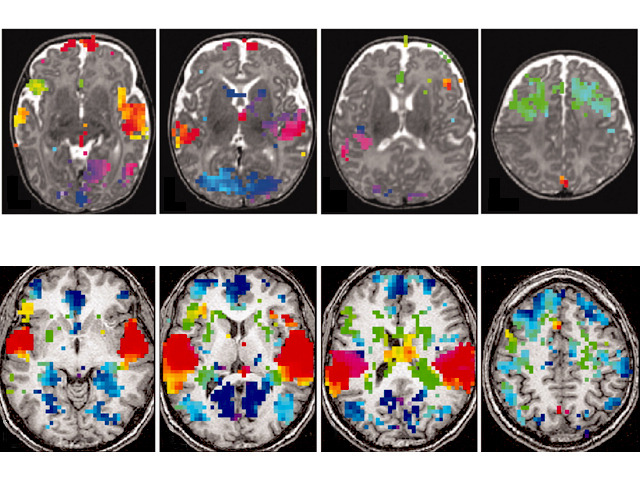

Babies start talking when they are about a year old, but their brains are primed to detect language long before that. Here, researchers have used fMRI scanning to compare the brain of a three month old baby (above) to an adult brain (below). The colours show the order in which different parts of the brain are active when a short sentence is heard (the sequence goes red – green – blue). The baby’s brain is not yet fully developed, but it shows roughly the same patterns of brain activity that are important in adult speech perception. Regions of the adult brain involved in speech production and grammar integration also light up in the baby’s brain, even though it can’t yet say a word, let alone a sentence. When the same sentence is repeated, brain activity increases in the baby, suggesting it can remember and recognise these sounds.